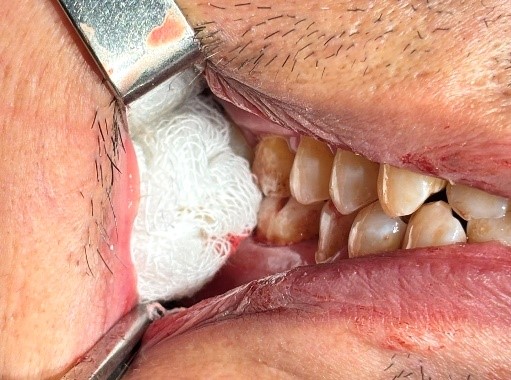

Ép gạc tại huyệt ổ răng chảy máu